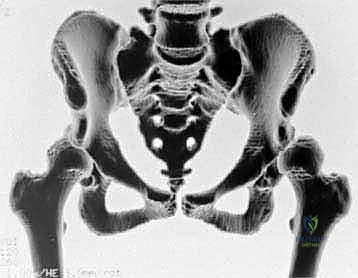

3. التصوير المقطعي المحوسب (CT Scan) ثلاثي الأبعاد: يوفر خريطة طوبوغرافية دقيقة للحوض، مما يسمح للجراح بالتخطيط الدقيق لمقدار وزاوية التدوير المطلوبة للتجويف الحقي.

4. إعادة التوجيه والتدوير (Rotation & Redirection)

باستخدام أدوات خاصة، يقوم الدكتور هطيف بتدوير التجويف الحقي الحر في ثلاثة أبعاد (للأمام، وللخارج، وللأسفل) حتى يغطي رأس عظم الفخذ بشكل مثالي وميكانيكي سليم. يتم التحقق من الزاوية الجديدة فوراً داخل غرفة العمليات باستخدام جهاز الأشعة السينية المتحرك (C-arm).

5. التثبيت القوي (Fixation)

بمجرد الوصول إلى الوضع المثالي، يتم تثبيت العظام في مكانها الجديد باستخدام براغي معدنية قوية من التيتانيوم أو دبابيس (K-wires). هذا التثبيت يضمن التحام العظام بشكل صحيح خلال فترة التعافي.